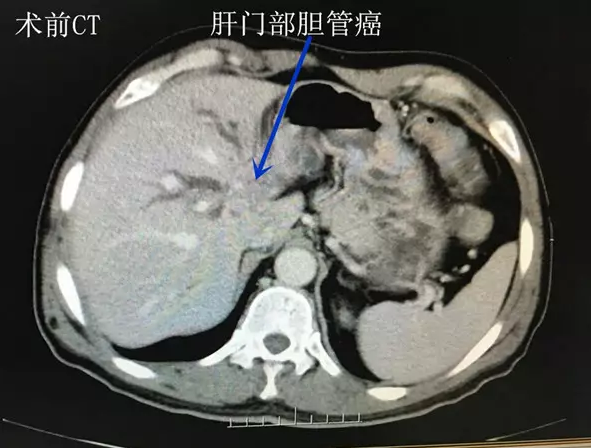

3月22日,王先生慕名来到郑州大学五附院就诊。肝胆胰腺外科主任李晓勇教授接诊后,制定了详细的诊疗方案,完善CT及MRI考虑:左肝管及肝总管汇合区占位性病变,大小约13mm*25mm,胆红素高达486.7umol/L,为重度梗阻性黄疸。初步考虑为肝门部胆管癌。

近日,王先生来郑州大学五附院肝胆胰腺外科复诊。黄疸消退,饮食较前明显好转,大小便也恢复正常,体重较前增加5kg。CT显示:肿瘤消失(术后CT图),行T型管造影,胆管通畅(胆管造影图)。王先生说:“手术前,黄人一个;而如今面色红润,能吃能睡,逛街游玩样样行。”